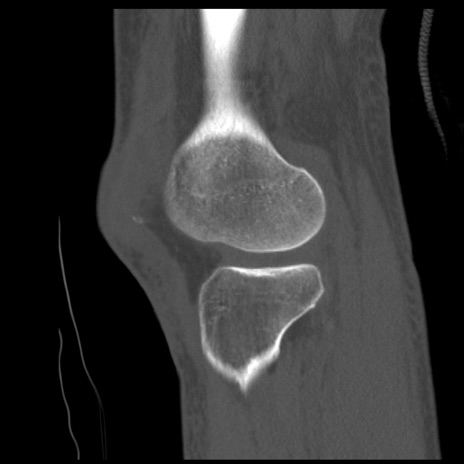

症例28 右膝関節CT(矢状断像)

右膝関節CT